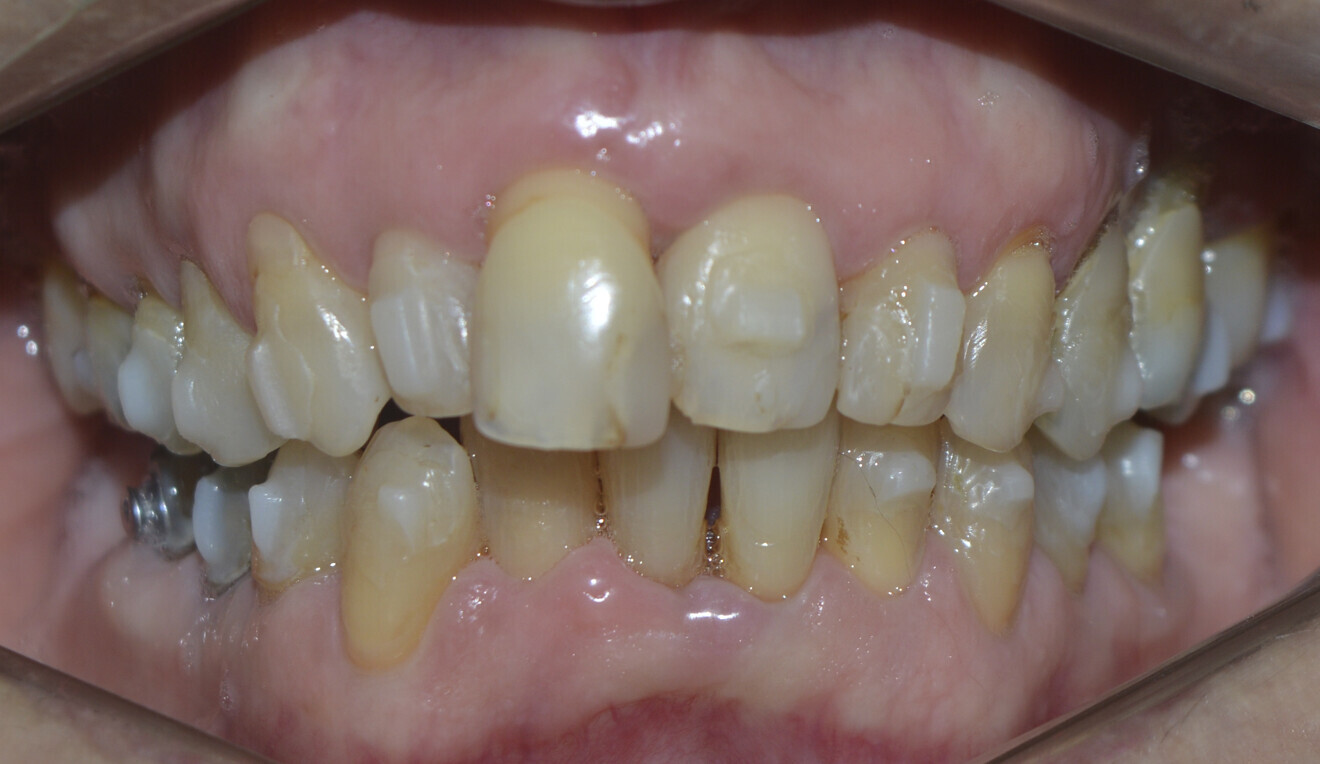

The periodontal treatment of an adult patient undergoing treatment with aligners is illustrated in demonstration of these points. Orthodontic planning considered the extra-oral photographs (Fig. 1) and intra-oral photographs (Figs. 2 & 3). Intra-oral scanning (Fig. 4) and radiographic documentation using panoramic radiographs and cephalometric radiographs (Figs. 5 & 6) were also carried out. From a periodontal perspective, periapical radiographs were recommended (Fig. 7), as this was an adult patient who smoked and showed clinical signs of advanced periodontal disease. Prior periodontal treatment was carried out (Fig. 8) to begin treatment with aligners (Fig. 9).